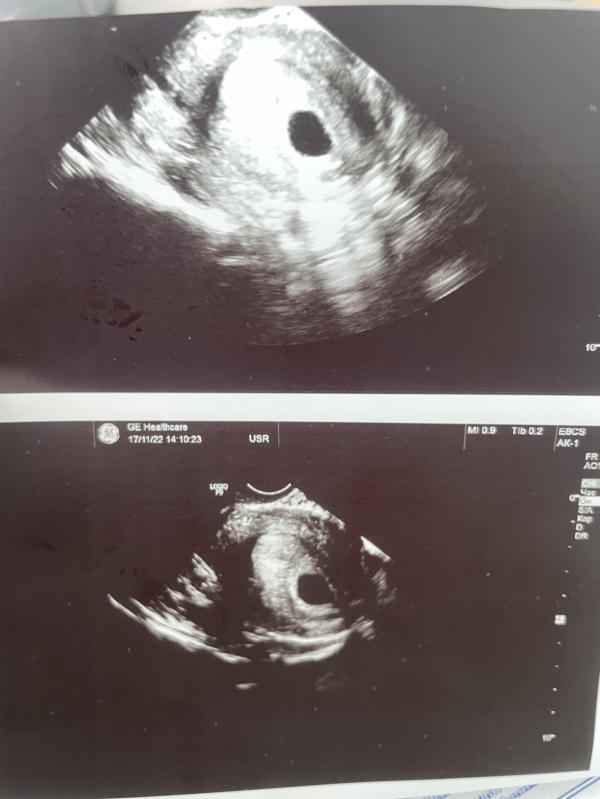

Мамочки я так переживаю😓Сегодня прошла УЗИ гинекологические ,ПМ-05.10.2022,говорят эмбриона еще нету ,сердцебиение тоже -,еще свободная жидкость на матке 🤦🏻♀️у кого была такое ? Сильно переживаю,Рекомендовано контр узи через 10дней

У меня было такое, тоже пошла через неделю и тогда все показало, такой знакомый снимок😍😍😍😍 божечки

На этом УЗИ сколько недель плоду было тогда